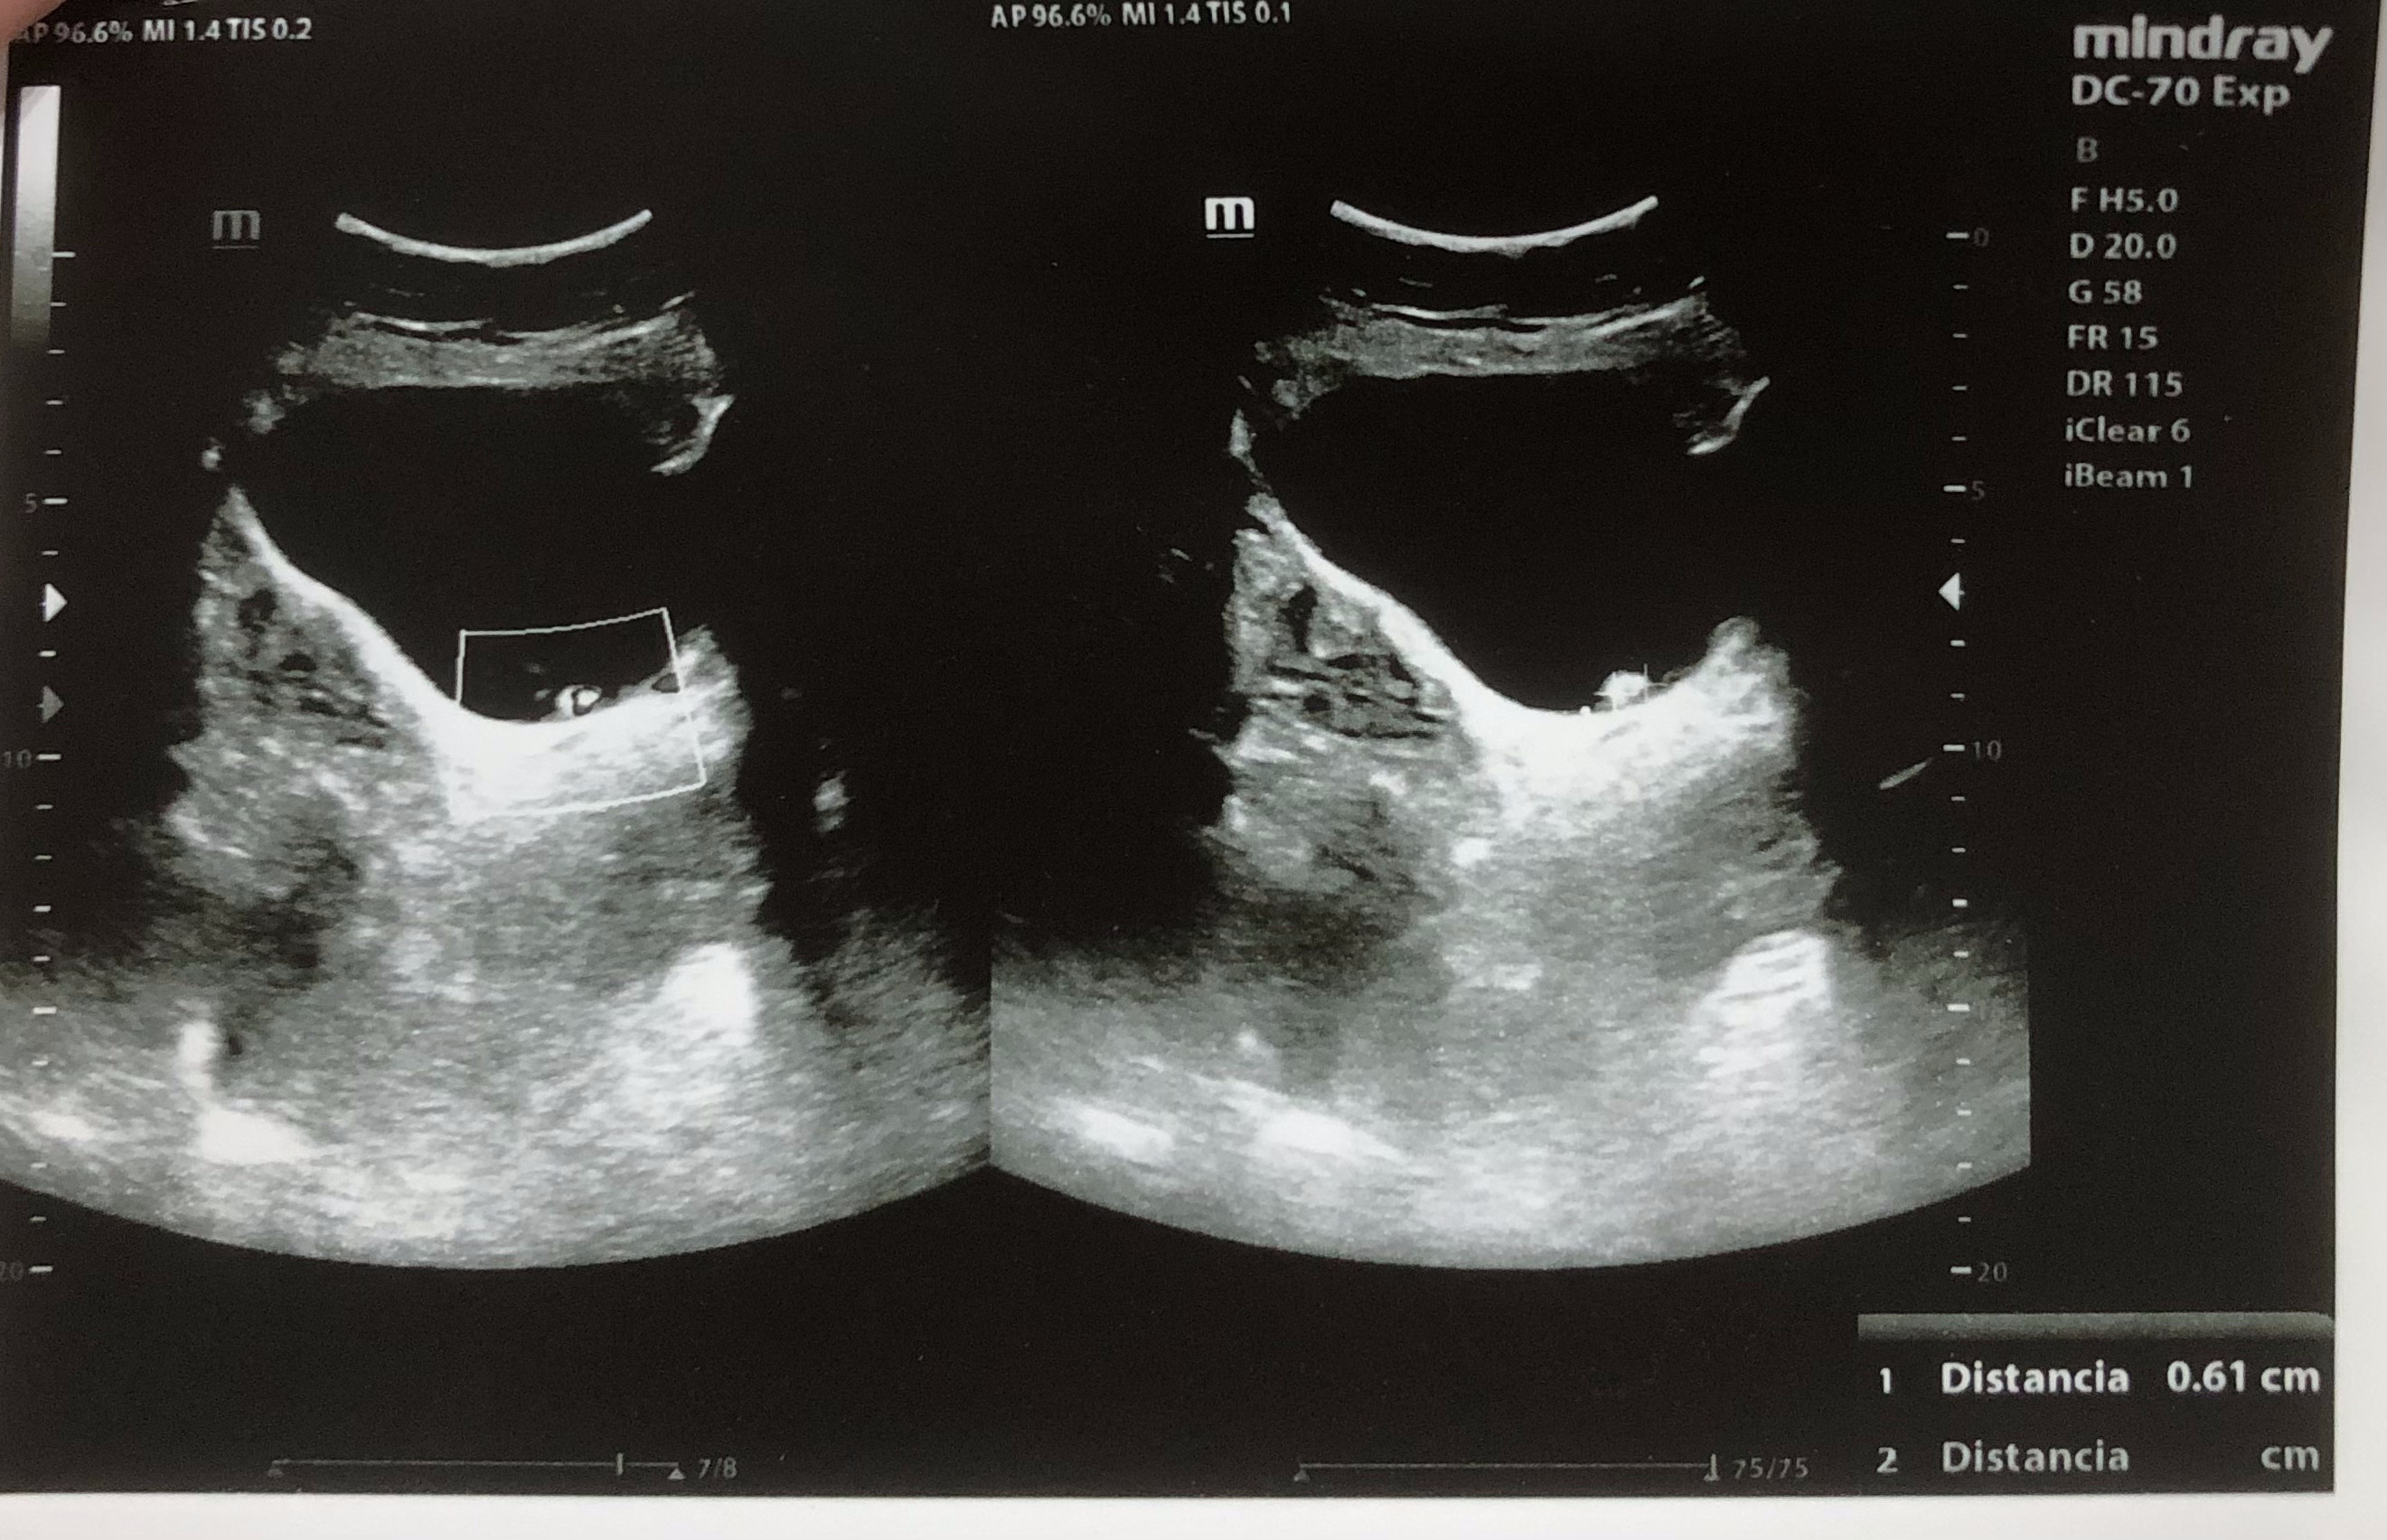

Se realiza ecografía renal donde se aprecia lesión hiperecogénica redondeada en pared inferior derecha de vejiga sin sombra posterior de 0,7 x 0,61 cm, que no se moviliza con cambios posturales de la paciente. Centelleo dudoso.

En urianálisis se aprecian hematíes 25/uL con proteínas negativas. Resto de analítica sin alteraciones.

Litiasis vs lesión de características malignas.